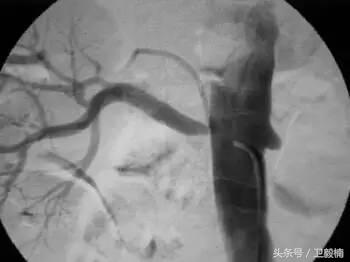

(1)经皮肝穿胆道引流(Percutaneous transhepatic choledochus drainage,PTCD或PTD)由于恶性(如胆管癌、胰头癌)或良性(如总胆管结石)病变,引起肝外胆道梗阻,临床出现黄疸。PTCD可行胆道内或胆道外胆汁引流,故而缓解梗阻,减轻黄疸,为根治手术提供有利条件。行PTCD前需先做经皮肝穿胆管造影(Percutaneous transhepatic),确定胆管梗阻的部位、程度、范围与性质。PTCD有内外引流之分,通过PTC的穿刺针引入引导钢丝,而后拔出穿刺外地,沿引导钢丝送进末段有多个侧孔的导管,导管在梗阻段上方的胆管内,其内口亦在该处,胆汁经导管外口连续引流,是为外引流;若导管通过梗阻区,留置于梗阻远端的胆管内或进入十二指肠,胆汁则沿导管侧孔流入梗阻下方的胆管或十二指肠,是为内引流。

(2)经皮肾穿肾盂造瘘术(Percutaneous transrenal pyelotomy) 主要用于尿路梗阻引流,也可利用造瘘术的导管将肾盂或输尿管内结石向下推移,送至膀胱排出。造瘘术方法同上,使用细针经皮穿肾,进入肾盂,先做经皮顺行肾盂造影(Percutaneous antigrade pyelography)观察尿路形态、狭窄或梗阻部位及其程度,而后沿穿刺针送进引导钢丝,再将导管插入,留置于肾盂内。